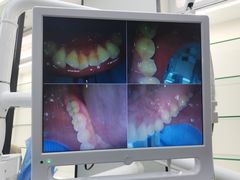

• 牙博士口腔品牌连锁(杨浦店)

• -牙博士口腔品牌连锁(杨浦店)

pudding蕊_4175 | 20-12-27

报错